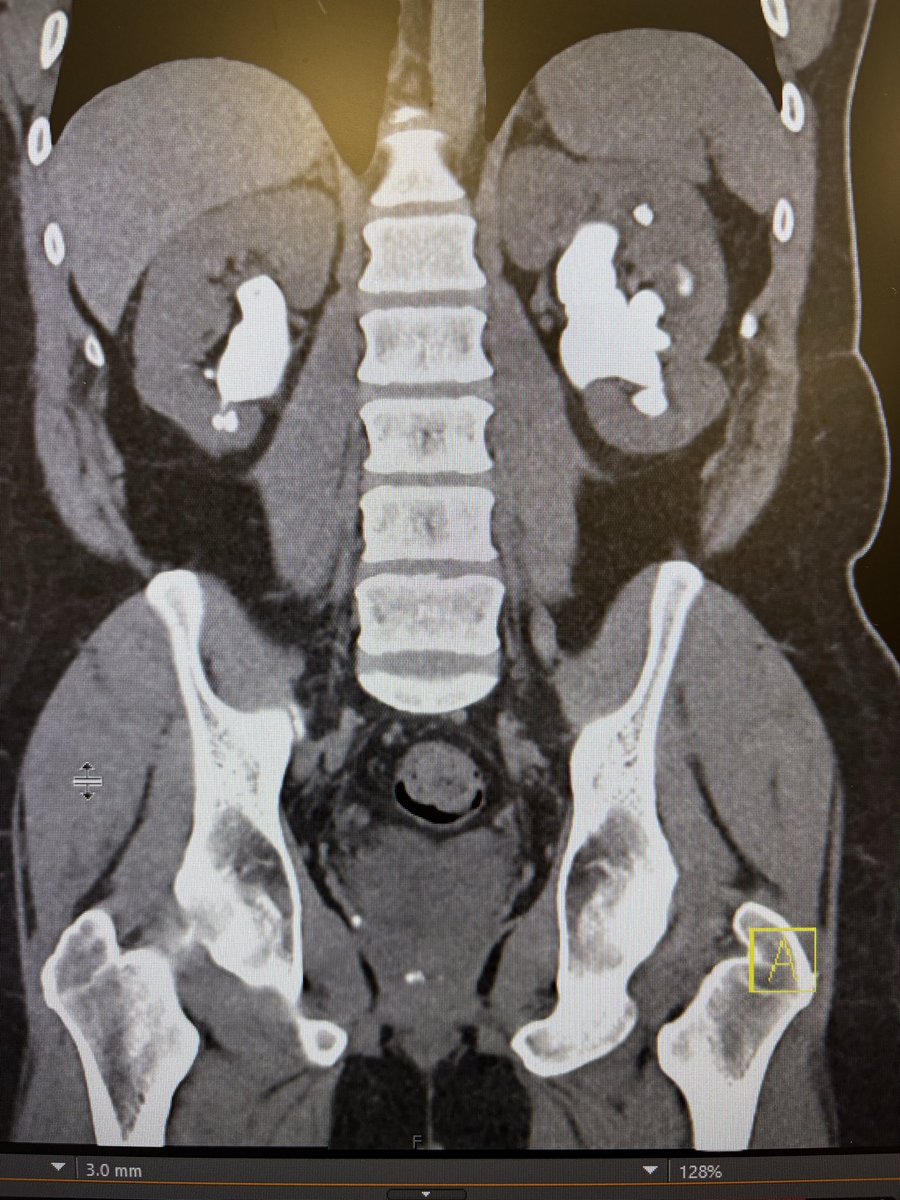

Bilateral PCNL for cystine staghorn calculi. Even with the trilogy the case took 5 hours. Although FANS is amazing there is still a place for PCNL. @NM_Urology @EndourologyNm